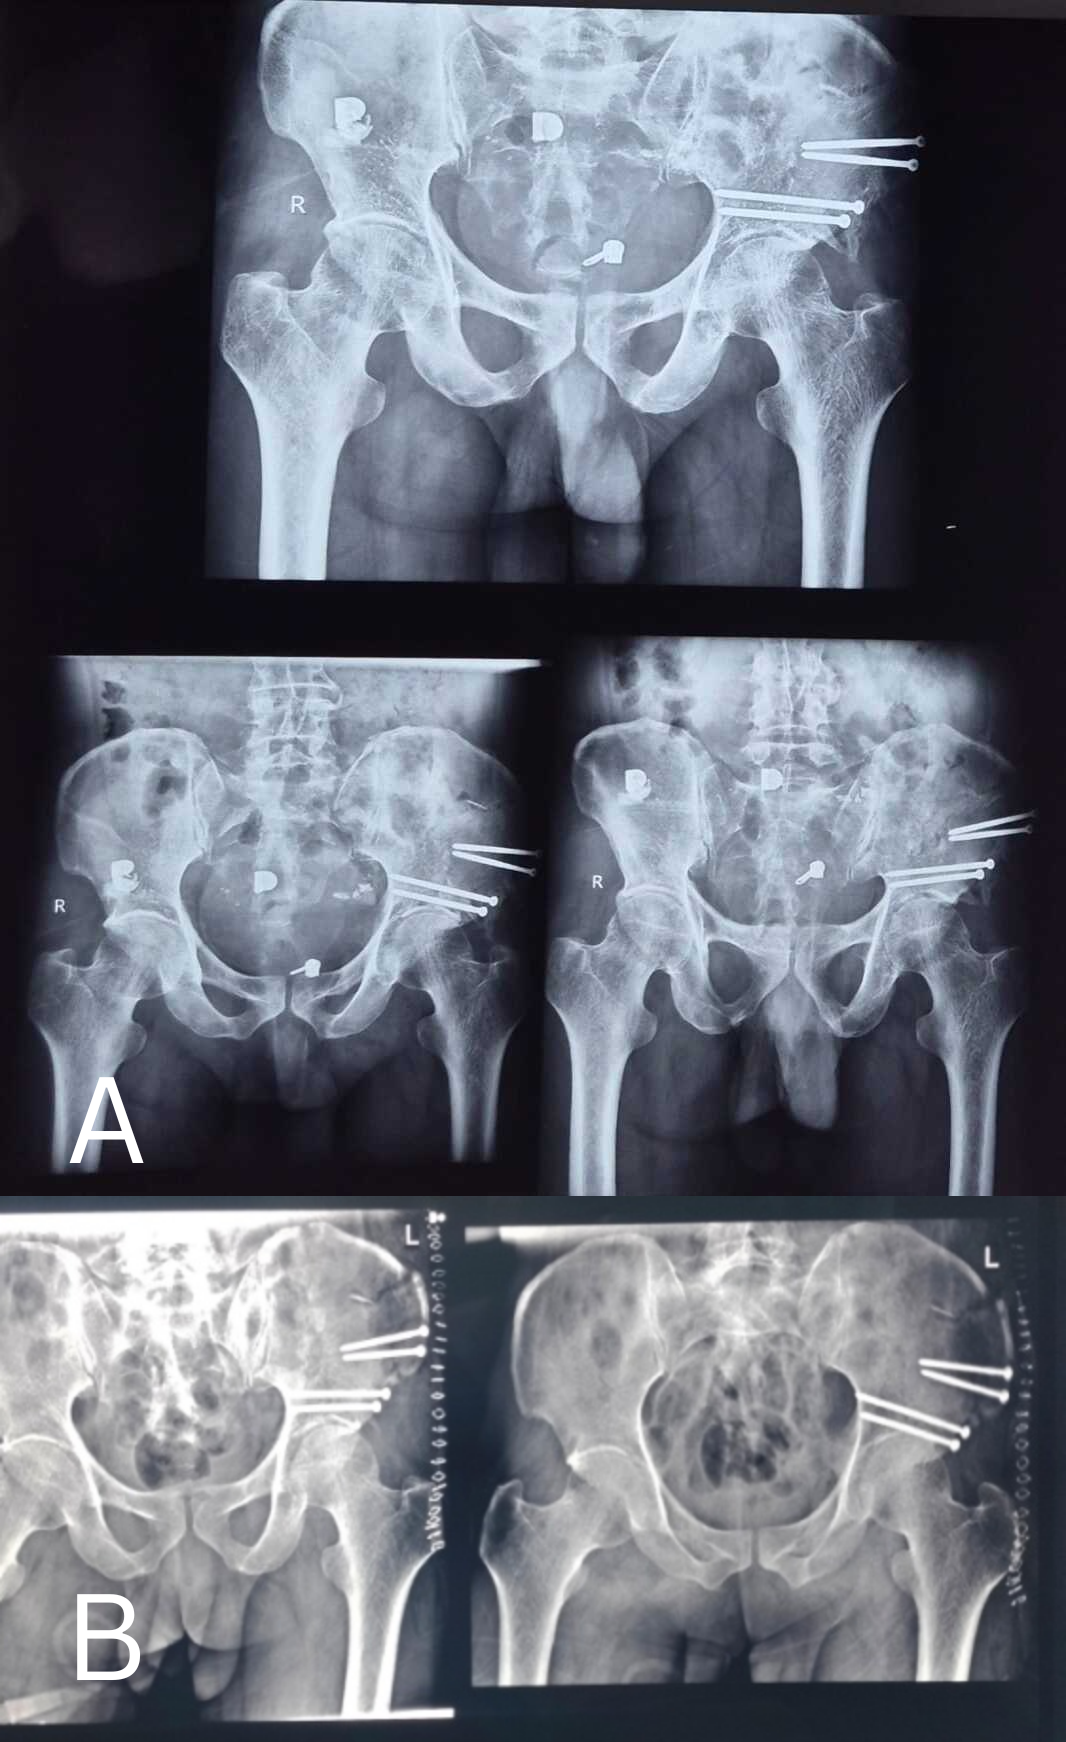

Mr. S., aged 52, was found lying beside the road in an inebriated manner, and was referred from multiple centres, leading to a 2½ week delay in treatment. X-rays showed a superior type fracture of the right acetabulum (Fig. 1).,

Figure 1: (a) Three months post-operative X-ray of the pelvis (b) Immediate post-operative X-ray of the pelvis.